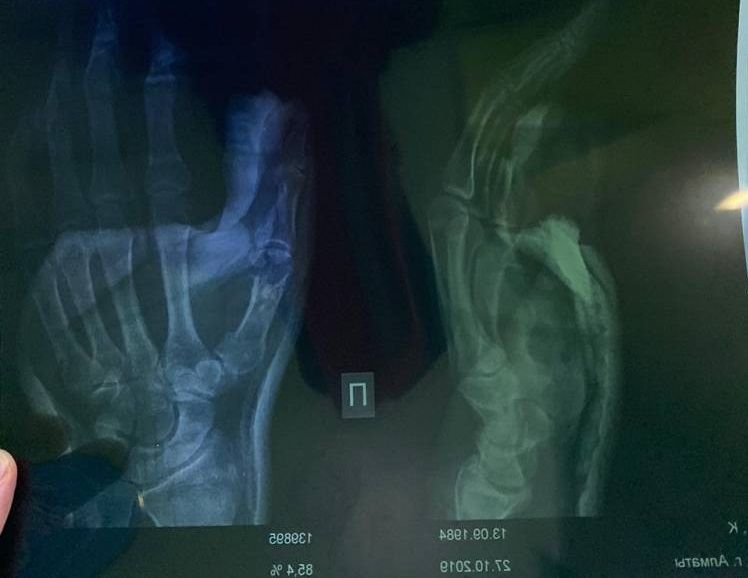

Vesti.kz белгілі болғандай, қазақстандық боксшы жетінші раундтан бастап сынған қолымен жұдырықтасқан. Нақтырақ айтқанда, Қанат Исламның оң қолының білегіне зақым келген. Осы себепті боксшы жекпе-жектің соңына дейін жойқын соққы жасай алмай, қарсыласынан алыс жұдырықтасты. Жекпе-жектен соң Қанат Исламды бірден ауруханаға жеткізіп, қолына гипс салған.